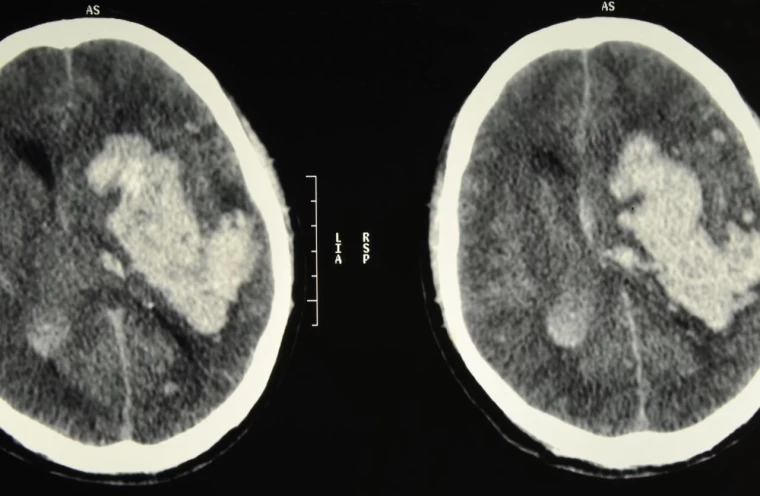

Beyin kanaması, aniden gelişen ciddi bir tıbbi durumdur ve beynin içerisindeki kan damarlarının patlaması sonucu meydana gelir. Bu durum, beynin normal fonksiyonlarını bozan bir basınca yol açar. Genellikle bir travma veya yüksek tansiyon gibi sebeplerden kaynaklanan beyin kanaması, anında müdahale gerektiren ve ölümcül sonuçlar doğurabilecek bir durumdur. Beyin kanamasının belirtilerini ve nasıl anlaşılabileceğini anlamak, erken müdahale şansını artırır. Bu yazıda, beyin kanaması belirtileri ve bu durumun risk faktörleri hakkında detaylı bilgi vereceğiz.

Beyin kanaması, hemen her zaman tehlikelidir, ancak bazı durumlarda daha büyük riskler taşır. Özellikle kanamanın büyük olduğu ve beyin dokusuna ciddi baskı yaptığı durumlar son derece tehlikelidir. Kanamanın gerçekleştiği bölge de önemlidir. Beynin hayati fonksiyonları kontrol eden bölgelerinde meydana gelen kanamalar, solunum durması, kalp atışı düzensizliği ve bilinç kaybı gibi ölümcül sonuçlara yol açabilir. Eğer beyin kanaması erken fark edilmez ve tıbbi müdahale gecikirse, kalıcı beyin hasarları veya ölüm riski artar.

Beyin kanamasının ilk belirtileri, kanamanın yerine ve şiddetine bağlı olarak değişir. Ancak genel olarak, ani ve şiddetli baş ağrısı en yaygın belirtidir. Bunun yanında bulantı, kusma, görme bozuklukları, konuşma zorluğu, denge kaybı, yüz veya vücutta ani uyuşma ve bilinç bulanıklığı da görülebilir. Bu belirtiler, özellikle ani ve beklenmedik bir şekilde ortaya çıkıyorsa, derhal acil tıbbi yardım alınmalıdır. Zamanında müdahale, beyin kanamasının yol açabileceği kalıcı hasarların önlenmesinde kritik rol oynar.